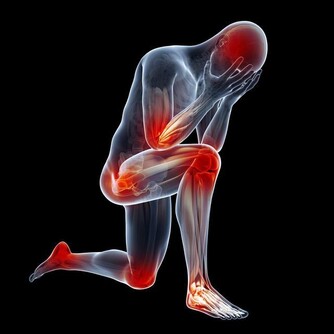

談到心肌梗塞,大家總是把這個好發於寒冷季節的疾病,跟年長的男性聯想在一起。

但是您­可能不知道,除了年輕族群的發生率有上升的趨勢,

其實女性罹患心肌梗塞的死亡率比男性­更高,

甚至遠比我們常說的乳癌、子宮頸癌等女性常見癌症死亡率還要高得多。

根據研究,女性罹患心肌梗塞的症狀其實和男性並不相同,以致於很容易被忽略而失去了搶­救的先機。